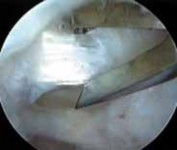

TECHNIQUES A B C D E F G H I ### FIG 4 • A–G. The iliopsoas tendon of the right hip is exposed from the peripheral compartment. A. The initial tendon viewed through a capsular window is fully identified, but is abnormally small. B. This tendon is released with a basket. C. A stump remains. D. This is resected with a shaver. E. Further dissection exposes a more substantial portion of the iliopsoas tendon. F. This is released as well. G. Complete release of the bifid tendon is documented. H,I. Viewing the iliopsoas tendon of a right hip at its insertion on the lesser trochanter within the iliopsoas bursa. H. A bifid iliopsoas tendon is identified with medial (

) and lateral () bands separated by a vessel (

two white asterisks

) coursing perpendicular. I. The lateral band (

black asterisks

) has been released with a flexible RF device, revealing the medial band (

white asterisk

) which subsequently is released. (Courtesy of J. W. Thomas Byrd, MD.)**